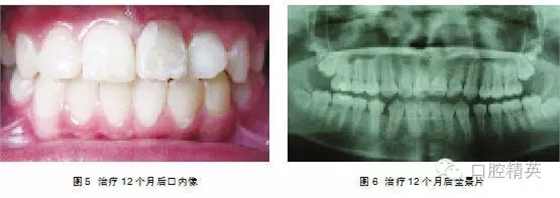

處理:2004年3月行外科開窗+正畸牽引治療,7個月后檢查:1|已萌出,未完全到位,1|唇側(cè)牙根處稍隆起,即為彎曲的牙根。因1|為彎根比較嚴重,如完全排齊有可能使牙根暴露,故未完全排齊(圖4、5)。

典型病例3:患者,男,11歲,因—1未萌來我院就診(圖1)。

檢查: |1未萌,1|全萌,1|2之間間隙為5mm。X線片示: |1骨內(nèi)埋伏,倒置,埋伏牙倒置角度在130°,牙冠的腭側(cè)面向外,稍彎根,1| 牙根基本形成(圖2~4)。

處理:行外科開窗+正畸牽引治療,6個月后破齦萌出,連續(xù)牽引,12個月后到位(圖5~7)。